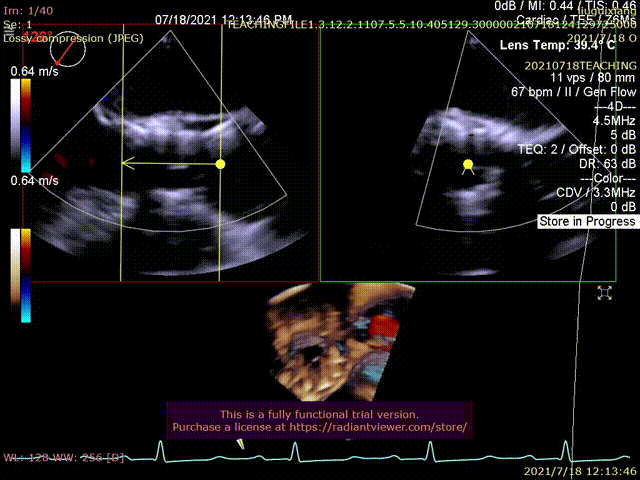

食道超声辅助瓣膜定位

超声提示形态及血流动力学欠佳

超声评估,形态及血流动力学良好